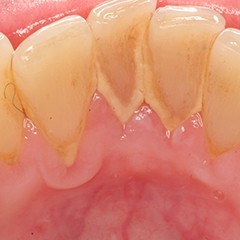

Tartar is the hard calcified material that builds up on teeth. It is formed mainly from minerals in saliva mixed with the bacteria of dental plaque. It can only be removed by a dental professional. We provide Emergency Dental Services in Mount Prospect like Abscess-Gum & Dental Abscess, Calculus Teeth, Chipped Tooth, Erosion, Fillings, and Gum Disease, Jaw Injury, Periodontitis, etc. Contact us at 847-728-8417 for more information.